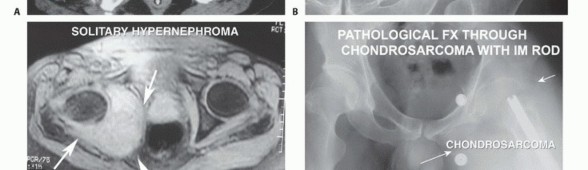

The primary indication is a nonmetastatic bone or soft tissue sarcoma (e.g., chondrosarcoma, osteosarcoma, pleomorphic sarcoma) that has failed neoadjuvant therapies or is too massive for limb-sparing surgery. Tumors involving the sciatic nerve and posterior buttock may necessitate an anterior flap hemipelvectomy, whereas massive anterior thigh tumors require a posterior flap.

Contamination of Surrounding Structures

Inappropriate, poorly planned biopsies or unplanned intralesional excisions ("whoops" procedures) can contaminate multiple anatomic compartments. Similarly, pathologic fractures of the proximal femur with massive hematoma tracking can contaminate vast tissue volumes, precluding safe limb salvage and necessitating amputation.

Palliation and Nononcologic Indications

While rare, palliative hemipelvectomy may be indicated for intractable pain from lumbosacral plexus invasion, uncontrollable hemorrhage, or massive fungation in metastatic disease (e.g., solitary renal cell carcinoma metastasis). Nononcologic indications include catastrophic pelvic crush injuries, open hemorrhaging pelvic fractures, or chronic, life-threatening pelvic osteomyelitis/decubiti in paraplegic patients.